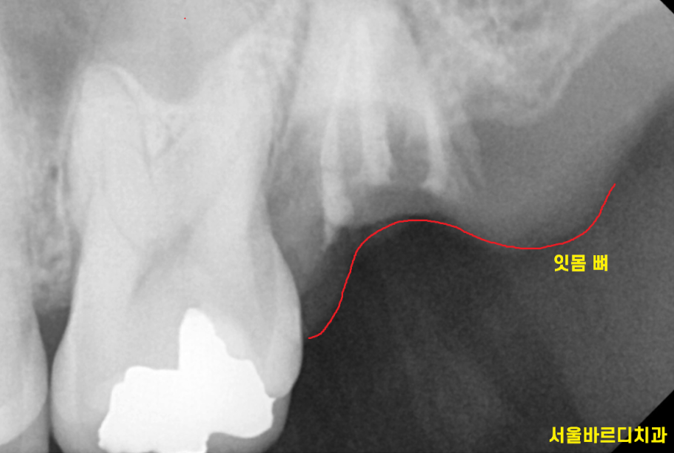

부러졌지만

1%라도 살릴 가능성이 있을지

작은 x-ray를 촬영하여 정밀검사를 해보았습니다.

감일동 치과는 자연치아를 살리는 것을

최우선으로 생각하니까요

혹시나 했지만 역시나..

신경치료까지 다 되어있는 상태네요~

잇몸 뼈 위로 머리가 일부분이라도 올라와 있으면 살려볼 수 있는데...

잇몸 뼈 안쪽까지 부러져서

살릴 수 없겠네요.

발치 후 임플란트가 필요했습니다.